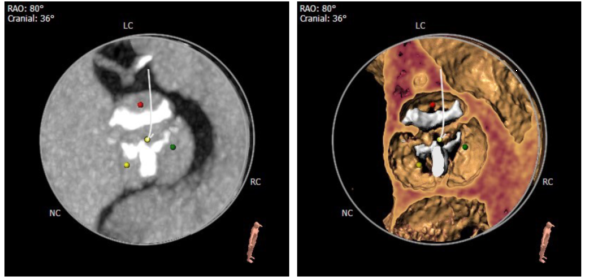

术前CT评估-主动脉窦及STJ

术前CT评估-冠脉开口高度